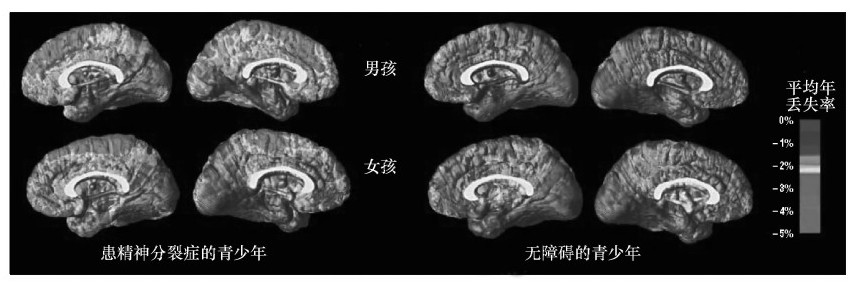

从生物学上讲,一项为期5年的研究发现,EOS儿童会比没有精神障碍的儿童丧失更多大脑灰质(Kranzler et al.,2006)。这种丧失同时出现在大脑两侧,并由前向后发展,这表明大脑功能出现了严重的生物学退化(Vidal et al.,2006)。从行为学上看,仅8%~20%的EOS患者所有症状都能获得缓解,大部分患者的症状会伴随终生(Eggers&Bunk,1997;Röpcke&Eggers,2005)。甚至与成年发病的精神分裂症患者或有其他精神病性障碍的儿童相比,EOS患者的损害也更严重。他们患病期更长,需要更长期的精神病护理,社会功能及独立生活能力损害更大(Hollis,2000;Kranzler et al.,2006)。唯一让人乐观的是,EOS的智商稳定,甚至在发病13年后仍然如此(Gochman et al.,2005)。很明显,这种病起病越早,预后越差。

所有青少年都会经历突触修剪。然而,如上面功能性磁共振成像图所示,早发性精神分裂症患者该过程的发展速度非常快。洋红色表示神经元丢失最多的区域,蓝紫色表示神经元丢失最小的区域。 在上排图中(13岁),神经元丢失最多的区域在前额叶,该区域通常与推理和问题解决有关。5年后,18岁时(下排),神经元丢失涉及的区域更广泛,涵盖了几乎所有的大脑区域。